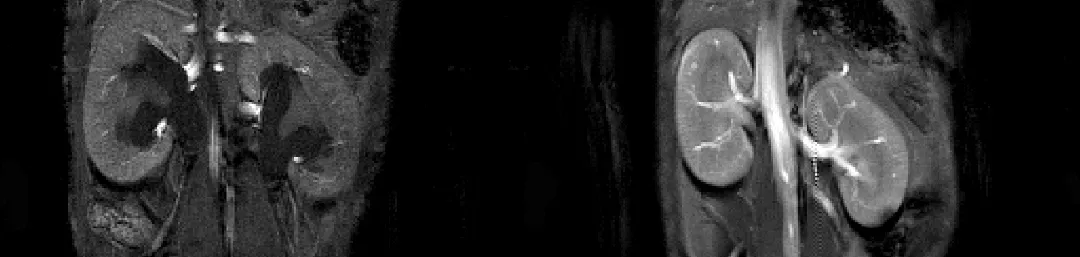

An overview of the research goals, current research projects, and principal investigators of the HART research theme. Image HART is a cohesive critical mass of hypertension and renal scientists with >£10 million of current funding from major UK funding bodies & industry partners. Publishing 250 papers in the past 5 years, our prize-winning scientists have a world-leading track record of discovery biology translating through to guideline-changing clinical trials. Our strategy is to identify important molecular mechanisms, focussing on the interactions between hypertension (salt appetite project) (salt-sensitive hypertension project), inflammation & vascular dysfunction (genetic modifiers of kidney disease project) that will eventually lead to fibrosis (kidney injury and resolution project), a common endpoint of all chronic diseases. This focus on early event biology, coupled with enhanced clinical biomarker discovery (retinal optical coherence tomography project), makes preventative intervention a realistic outcome. Parallel interrogation of kidney development using bioengineering makes repair and regeneration a viable alternative for CKD. salt appetite project salt-sensitive hypertension project genetic modifiers of kidney disease project kidney injury and resolution project enhanced clinical biomarker discovery retinal optical coherence tomography project HART Research Projects Current research projects within the Hypertension & Renal Theme (HART). HART Research Groups A list of the current PI-led Research Groups within the HART research theme. Image Image 1 - Live GFP-positive JG cell, taken on the spinning disk – picture courtesy of Charlotte Buckley.\nImage 2 – Human renal proximal tubule cells stained with Phallodin and DAPI, taken on the spinning disk – picture courtesy of Sarah Finnie.\n Current theme research focus (i) Salt, hypertension and cardiovascular risk: new paradigms Our clinical hypertension research is world leading and underpinned by innovative scientific programmes that have helped shape a new understanding of salt homeostasis, blood pressure control and the role of hormonal/metabolic regulators1 2. Salt accumulation in tissues (vessels, skin, cardiac muscle) creates high salt microenvironments that are detrimental to cardiovascular health. We are using mass spectrometry to map salt microenvironments within the normal and injured kidney and defining the effect of salt on endothelial function, glycocalyx integrity and immune cell activation and polarisation. An integrated physiological approach is defining in vivo how dietary salt affects early-life development of renal dysfunction and how central control of salt-taste activates a systemic hypertensive cascade. (ii) Prevention & repair of renal injury We are exploiting novel models of renal injury (including optogenic approaches for targeted cell ablation) and cutting edge technology (e.g. bulk transcriptomics of mRNA & ncRNA from defined cell populations and single cells including renal immune cells) to identify pathways to inflammation and fibrosis and, importantly, those that contribute to repair. Targets are validated in vivo, e.g. miR-214 antagonism to prevent fibrosis, miR-92a to limit glomerular damage, inflammasome targeting. This research targets early interventions on the pathways to fibrosis in patients and we have developed urinary biomarkers to predict renal and cardiac outcomes in diabetes. Developing projects focus on the interaction between kidney and heart disease in pre-clinical models and patient cohorts, and improving cardiovascular risk stratification in renal patients. miR-214 antagonism to prevent fibrosis miR-92a to limit glomerular damage urinary biomarkers to predict renal and cardiac outcomes in diabetes the interaction between kidney and heart disease in pre-clinical models and patient cohorts (iii) Extra-cellular vesicle signalling in the kidney This project explores how kidney tubular function is regulated by the microRNA cargo of extracellular vesicles originating from the glomerulus and other regions of the nephron (intra-renal, urinary vesicles), and from distant organs, especially the liver (extra-renal, circulatory vesicles). This is a new physiological mechanism of inter-cellular/inter-organ signalling and represents a new target for treatment of kidney disease and its associated high cardiovascular risk. Vasopressin Regulates Extracellular Vesicle Uptake by Kidney Collecting Duct Cells (iv) Metabolic receptor pathways to renal vascular injury: P2X7 & GPR81 Structured bioinformatics has associated P2X7 (ATP receptor) and, more recently, GPR81 (lactate receptor) with renal vascular injury. Using hierarchical modelling we have evolved a novel hypothesis of ATP/P2X7 control of macro- and micro-vascular function, validated using in vivo approaches and BOLD-MRI. Moving to renal patients we have placed P2X7 on the interface between endothelial and immune cell function. Further clinical data place P2X7 in a subset of pericytes, a cell at the crossroads between hypoxia, EMT and fibrosis. Genomics shows a strong influence of genotype on P2X7 function, tractable with small molecules/biologics. GPR81 has a similar profile: gene knockout protects against renal injury. Hyperglycemia-induced Renal P2X7 Receptor Activation Enhances Diabetes-related Injury Inhibition of the purinergic P2X7 receptor improves renal perfusion in angiotensin-II-infused rats. Lothian Hypertension and Lipids Clinic NHS Lothian and the University of Edinburgh jointly run hypertension and lipid services across Lothian, discover what activities these services offer. Lothian Hypertension and Lipids Clinic Current Funders British Heart Foundation, Kidney Research UK, MRC, BBSRC, Medical Research Scotland, Wellcome Trust, Cunningham Trust, Diabetes UK Current Industrial collaborations AZ, GSK, Regulus Therapeutics, AbbVie, Idorsia, Pfizer Public Engagement My genes don’t fit! Living in a salt saturated society | Matthew Bailey | TEDxUniversityofEdinburgh This article was published on 2024-03-19